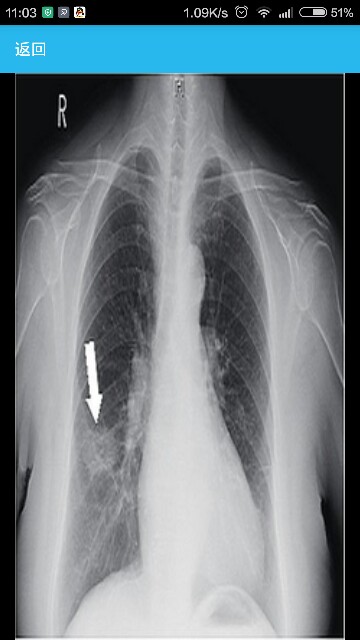

患者女性,70岁,因“间断发热4天,发现右肺占位1天”入院。 病史患者4天前受凉后出现发热,最高39.5℃,1天前出现咳嗽,咯少量棕色血痰,入院前1天查胸片示“右下肺占位”,收入院。既往心房颤动病史6年余。其父患肺癌去世。 临床表现体温39.8℃,脉搏100 次/分,呼吸频率22 次/分,血压125/80 mmHg。急性病容,右肺背部肩胛下角以下可闻细湿音。心界左大,房颤律。腹部查体未见异常。 辅助检查血常规:白细胞计数为12×109/L,中性粒细胞占86.6%,血红蛋白129 g/L,血小板240×109/L。尿便常规、肝肾功能及电解质正常。C反应蛋白(CRP) 98.0 mg/L。动态红细胞沉降率(ESR)71 mm。肺部肿瘤常规、降钙素原阴性、自身抗体阴性。超声心动示双房扩大。24小时动态心电图示心房颤动支气管镜检查,镜下正常,未见新生物。痰培养、痰涂片和病原体检测,痰细菌真菌培养、找抗酸杆菌阴性。支原体、衣原体、军团菌抗体阴性。痰涂片:革兰染色法白细胞计数>25/低倍视野、上皮细胞计数<10/低倍视野;革兰阳性球菌成对、中等量。基因芯片病原体检测:肺炎链球菌感染可能性为95%。影像检查,胸片:右下肺占位(图1);胸部CT:右下肺球形肺炎(图2)。 右下叶球形肺炎(肺炎链球菌感染可能性大),心房颤动。 治疗给予莫西沙星抗感染,体温降至正常,病变吸收消散出院(图)。